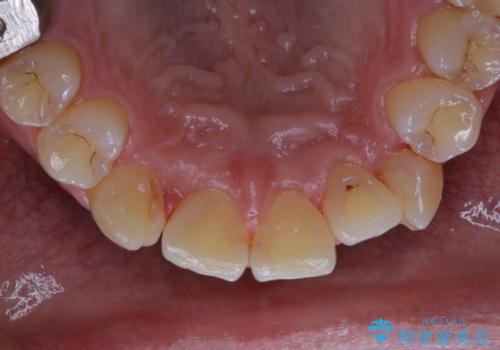

前歯メインにステインの付着が見られ、コース内容を相談した結果PMTC(保険外治療)の30分コースを行いました。

PMTCは30分コースと60分コースがあります。お口の中の状態を診断し適切なコースの説明・ご案内を行っています。